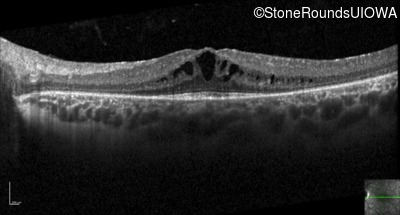

Optical Coherence Tomography - Right - 20/32

Exemplar / OCT Stack